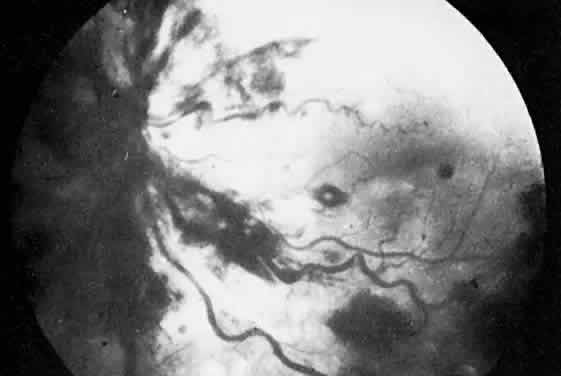

The ocular manifestations of antiphospholipid antibodies include retinal venous and arterial occlusions, amaurosis fugax, diplopia, and visual field loss.34,35 Extensive vasoocclusion, neovascularization, and vitreous hemorrhage may occur (Fig. 3). Treatment consists of photocoagulation for the neovascularization and systemic anticoagulation and immunosuppression. Vitrectomy may be required for vitreous hemorrhage. The role of systemic treatment of lupus anticoagulant in the management of ocular disease is unclear. Some investigators suggest that systemic anticoagulation be started promptly.36 The optimal duration of anticoagulation and whether antiplatelet therapy should be used are not known however. The optimal use of corticosteroids or other immunosuppressive drugs such as cyclophosphamide and azathioprine also is unknown. Two reports have found an association with the antiphospholipid syndrome and some additional retinal conditions. One report also has associated the primary antiphospholipid syndrome with central serous chorioretinopathy.37 In addition, lupus anticoagulant positivity could represent an additional risk factor for diabetic retinopathy according to a recent report.38